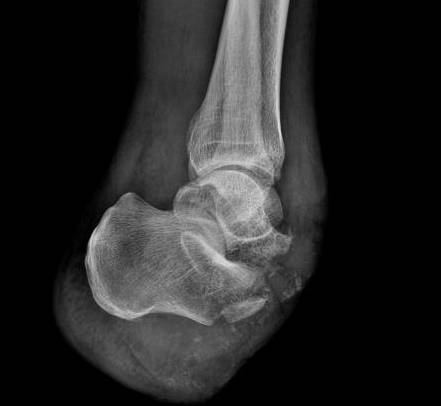

中前足截肢创面残留

跟骨需要特殊处理

微信图片_20170409220345.png

微信图片_20170409220330.jpg

Boyd截肢术:切除距骨,跟骨前移上移,与胫骨远端关节面融合。

Pirogoff截肢术:距骨切除,跟骨远端切除,跟骨翻转90°,垂直后与胫骨远端融合。